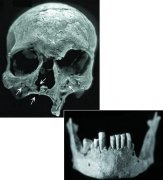

县皮肤病防治站卢绪剑站长对2018年莒县麻风病、性病防治工作进行汇报,并提出2019年工作计划。结合本县麻风病、性病工作实际,讲述了麻风病、性病流行病学特征,麻风病的传播途径、诊断和鉴别标准,麻风病的转诊程序和8大报病线索,以及梅毒的临床表现及5种性病的诊断和报病标准。做出相应让参训人员深层次的学习到麻风病、性病的临床表现及诊疗,以及各种皮肤病与麻风病的鉴别诊断,做到麻风病早发现、早诊断、早治疗;对性病做到准确诊断、规范治疗。